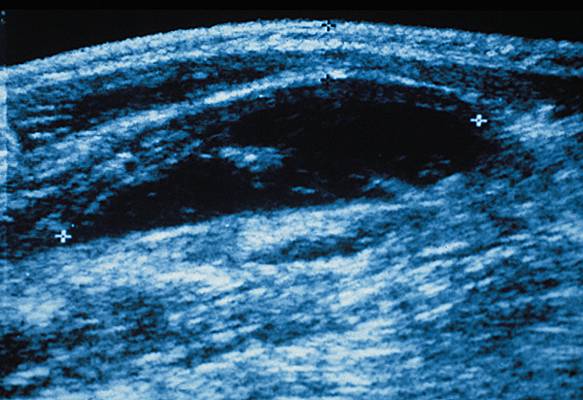

hématome

Collection de sang dans un organe ou dans un tissu, faisant suite à une hémorragie.